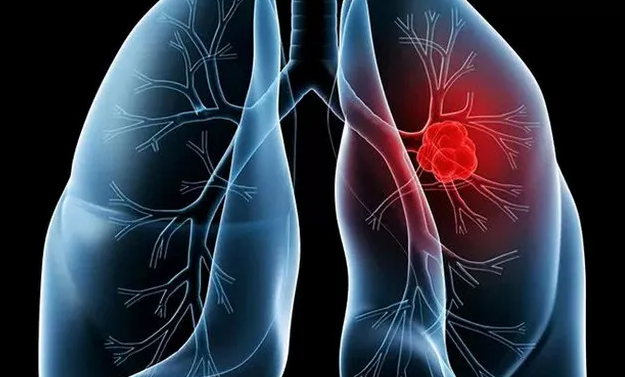

폐암이란 폐에 암세포가 무절제하게 증식하여 종괴(덩어리)를 형성하고 인체에 해를 미치는 것을 말합니다. 폐암은 폐에 국한되어 발견되기도 합니다. 하지만 폐암은 진행되면 반대쪽 폐뿐만 아니라 임파선이나 혈액을 통하여 뼈, 간, 부신, 신장, 뇌, 척수 등 온몸으로 전이될 수 있습니다.

폐암 초기증상

폐암 환자의 약 10%는 폐암 초기에 흉부 압박감 및 숨가쁨의 증상을 나타내며, 폐 기능이 상대적으로 안좋은 경우 호흡곤란의 증상이 더욱 심해집니다. 숨이 가빠지는 증상은 암 덩어리가 커지게 되면 폐에 압력을 가하게 되거나 암을 유발하는 체액(흉막액)이 흉강에 축적되면 숨가쁨의 원인이 됩니다.

6. 객혈

폐암이 발생하면 암세포가 기관지 점막을 침범할 수 있어 객혈 증상이 나타나게 되는데 일반적으로 객혈의 양이 많지 않고 환자가 기침이나 가래를 뱉을 때 객담에 피가 섞여 나옵니다. 이러한 유형의 객혈은 몇 주, 몇 달 또는 간헐적으로 지속될 수 있습니다.